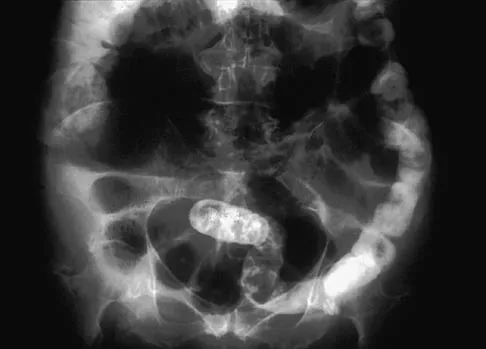

Figure 11 shows a consecutive sequence of MRI scans obtained in a 12-year-old boy who has had increasing lateral knee pain and catching for the past 6 months. Examination reveals pain localized to the lateral joint line. Range-of-motion testing reveals a 5-degree lack of full extension on the involved side. Plain radiographs and laboratory values are within normal limits. What is the most appropriate management?

Discoid menisci are rare causes of lateral knee pain in children. Various etiologies have been proposed, including failure of central absorption of the developing meniscus and hereditary transmission. Patients with discoid menisci have pain, clicking, and locking with a loss of active extension on range-of-motion testing. Classification of discoid menisci according to the Watanabe classification include complete, incomplete, and Wrisberg ligament type. The Wrisberg variant contains an abnormal posterior meniscal attachment. MRI is the diagnostic tool of choice, revealing a thick, flat meniscus generally seen in three consecutive MRI images. Symptomatic knees are often associated with a meniscal tear or degeneration and are managed with arthroscopic partial excision to a more normal shape (saucerization). Vandermeer RD, Cunningham FK: Arthroscopic treatment of the discoid lateral meniscus: Results of long-term follow-up. Arthroscopy 1989;5:101-109.